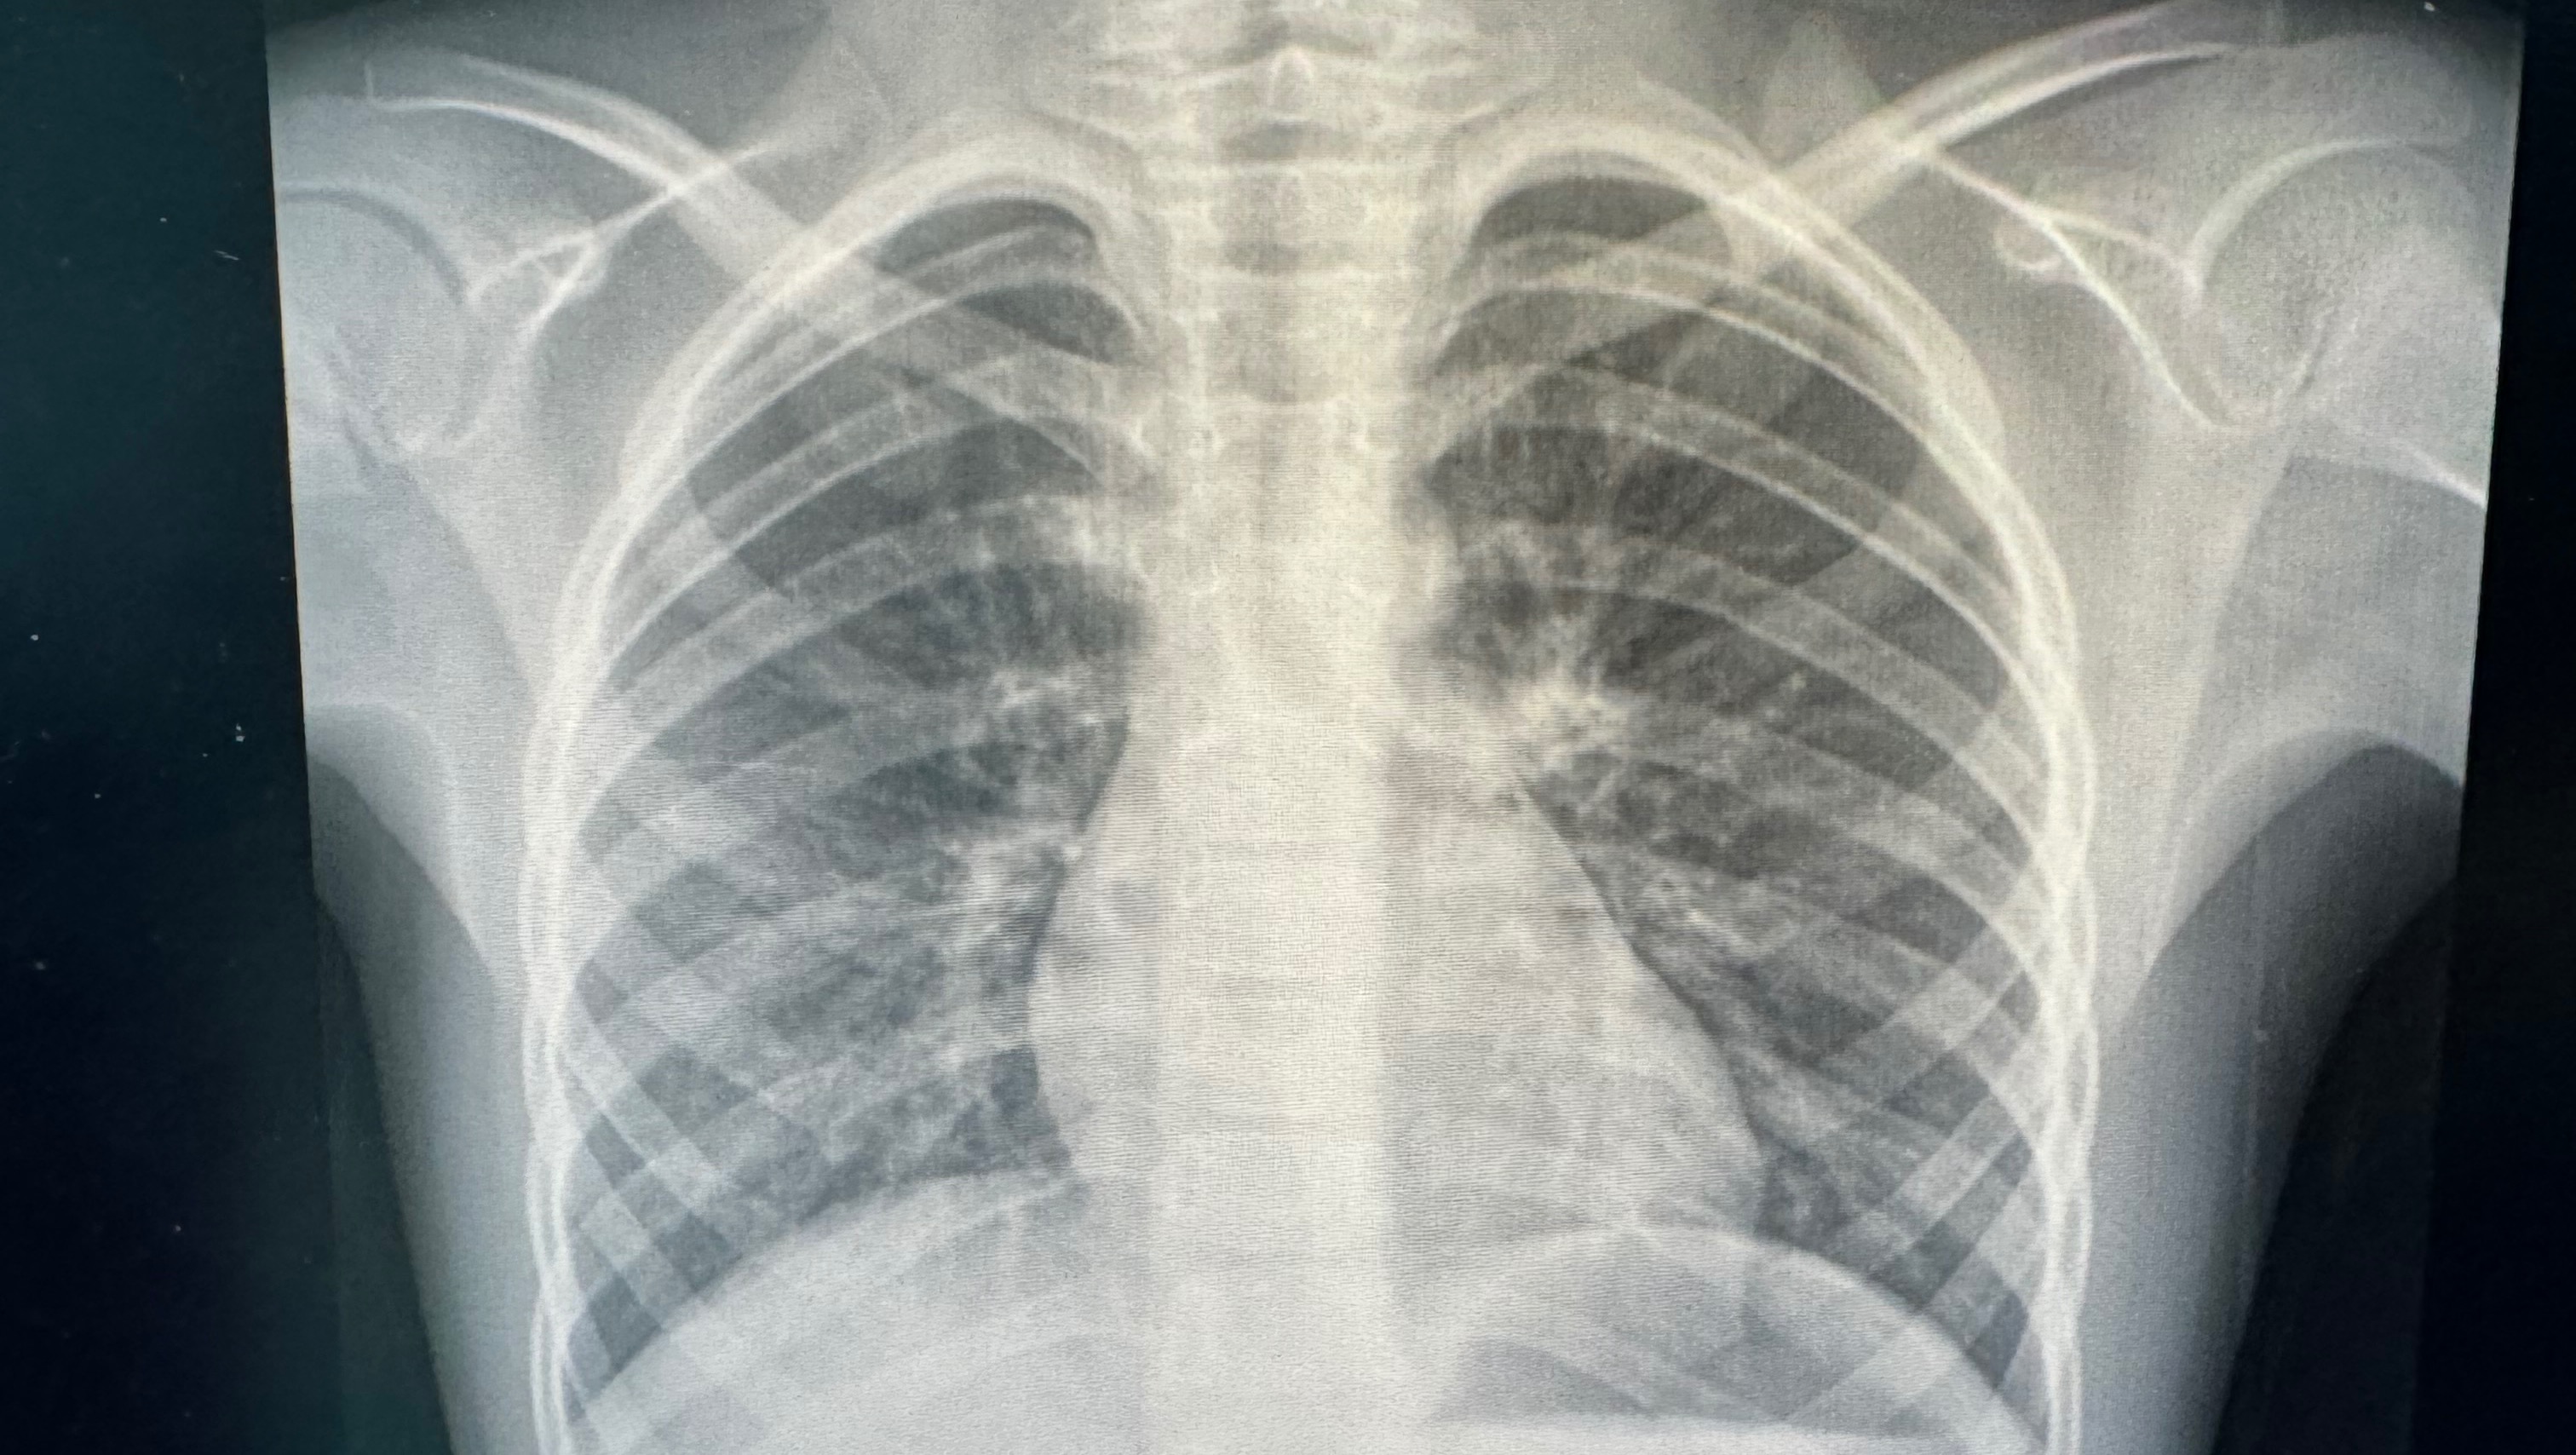

Hola mi nombre es Lia, estoy por cumplir 8 años y estoy recaudando fondos para poder solventar los gastos de mi tratamiento, desafortunadamente eh desarrollado un caso de asma grave, dermatitis atopica y rinitis alergica

Estas enfermedades han sido un desafio constante para mi y para mi familia, hemos enfrentado dias dificiles, pero no hemos perdido la esperanza. El asma y las demas enfermedades requieren tratamientos especializados y medicamentos muy costosos, lo que ah sido un gran estres financiero. A pesar de los constantes esfuerzos de mi mama por proporcionarme el mejor tratamiento posible mi condicion sigue siendo un desafio diario. Por eso quiero contar con su apoyo para poder solventar los gastos medicos y asegurar que tenga acceso a los tratamientos y medicamentos que necesito para mejorar mi calidad de vida. Tus donaciones seran utilizados para cubrir todos los gastos desde consultas, estudios y medicamentos.